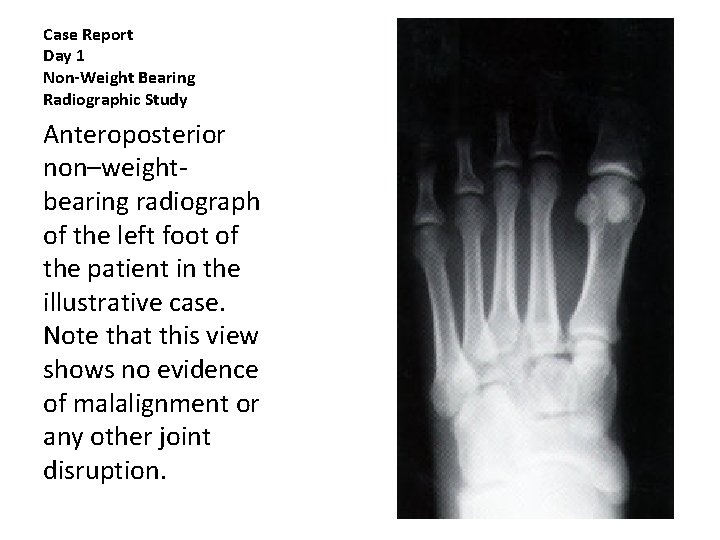

Case Report Day 1 • 20 year-old male • Injured left foot when thrown from sled • He landed with full weight on his left foot, which was folded under him • ER examination including radiographic study of left foot on day of injury • Impression negative for fracture • RX soft cast with foot placed in slight plantar flexion

Case Report Day 1 Non-Weight Bearing Radiographic Study Anteroposterior non–weightbearing radiograph of the left foot of the patient in the illustrative case. Note that this view shows no evidence of malalignment or any other joint disruption.